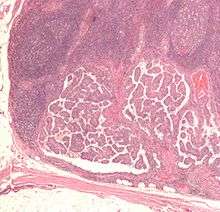

Micrograph of thyroid cancer (papillary thyroid carcinoma) in a lymph node of the neck. H&E stain

-